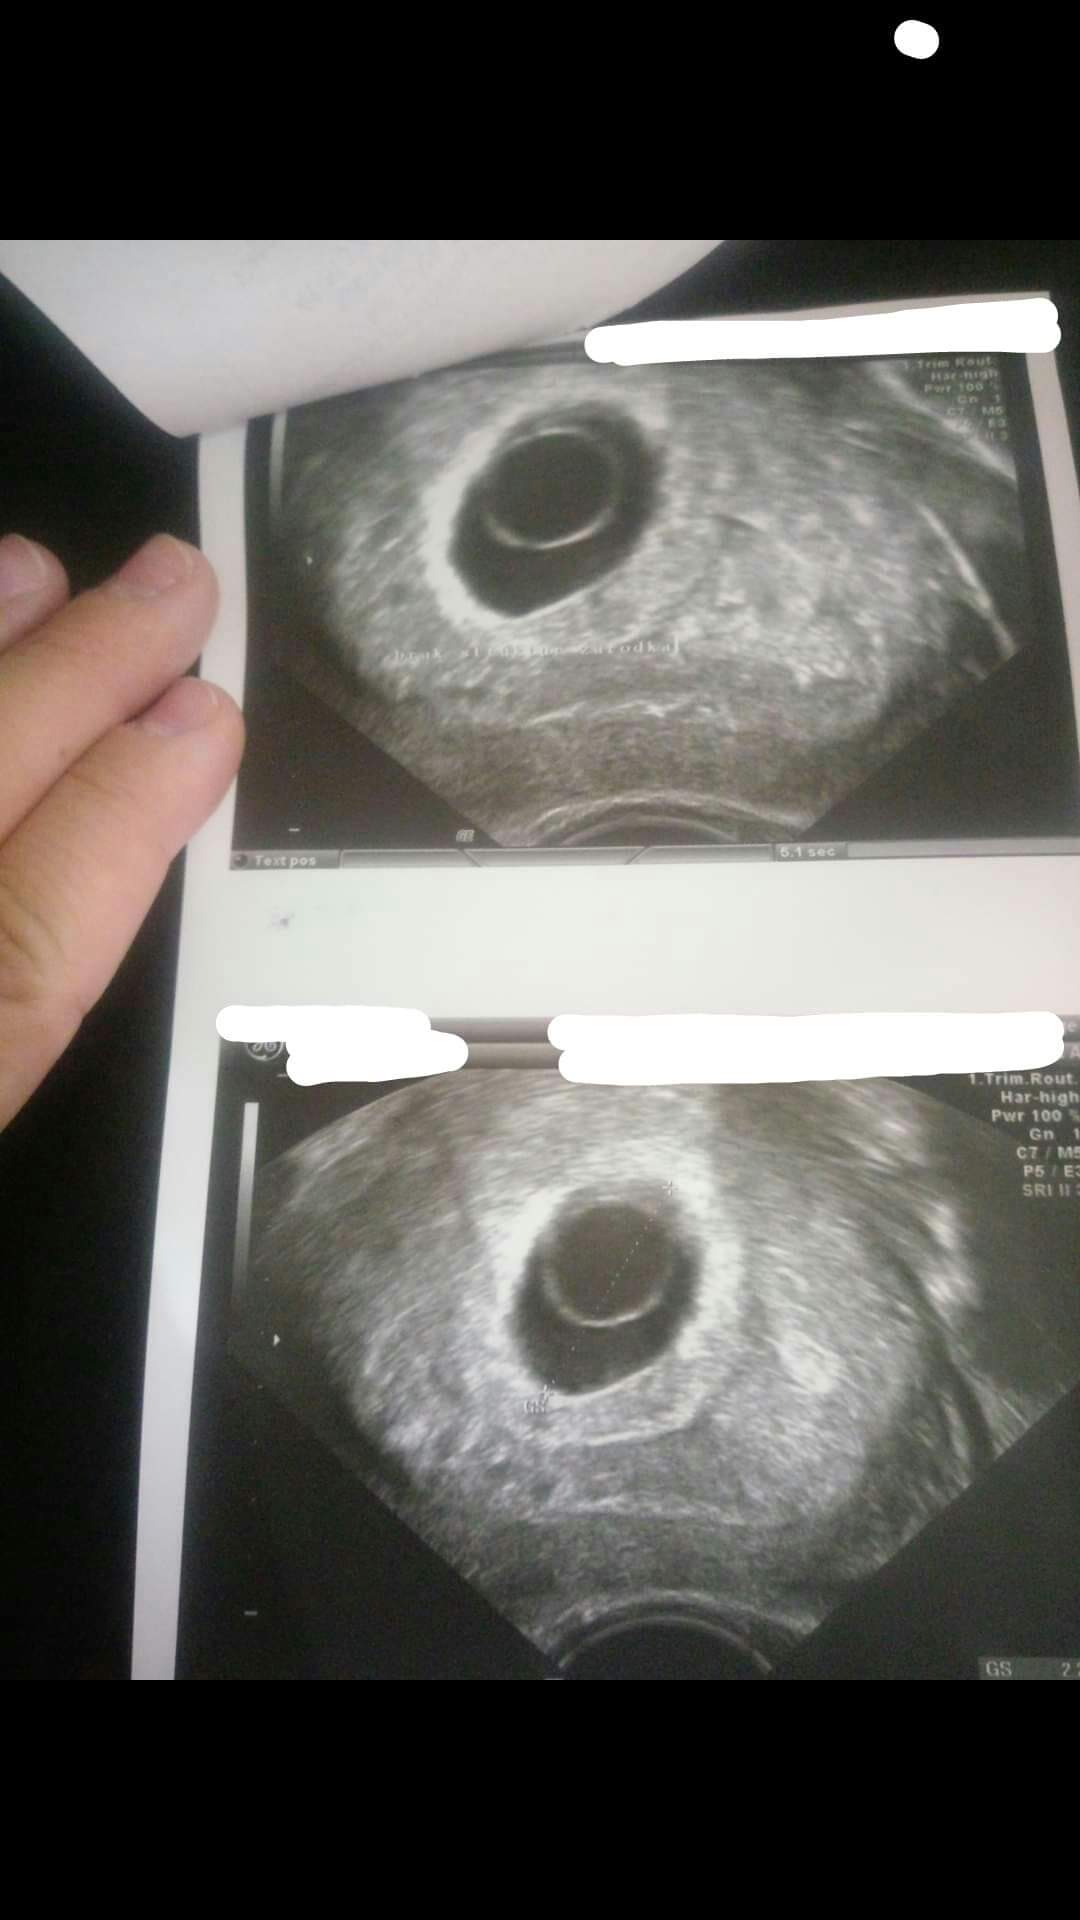

Hej, robiłam 10.06 beta hcg i wynik wyszedł 15500 z kolei 12.06 17500 czyli mały przyrost, według OM to 8 tydzień (7+6). Na wtorkowej wizycie nie widać było jeszcze zarodka. Czy ja niepotrzebnie panikuje? Czy któraś z Was byla w takiej sytuacji i wszystko skończyło się dobrze? Za mną 3 wizyty z których niewiele można wywnioskować..

Niestety, nie zawsze przy pęcherzyku zoltkowym pojawia się zarodek u mnie stwierdzili puste jajo płodowe mimo tego ze w pęcherzyku ciążowym był pęcherzyk zoltkowy, z tym ze on był przerośnięty miał 7,5 mm i nie było zarodka a miałam robione usg przez 3 lekarzy prywatnie plus w szpitalu przed podaniem tabletek poronnych..

proszę. tak to wygladalo